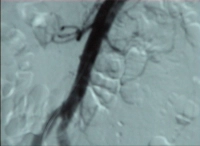

Filmbeispiel: abgangsnaher Verschluss der AMS mit Verschluss des Truncus coeliacus